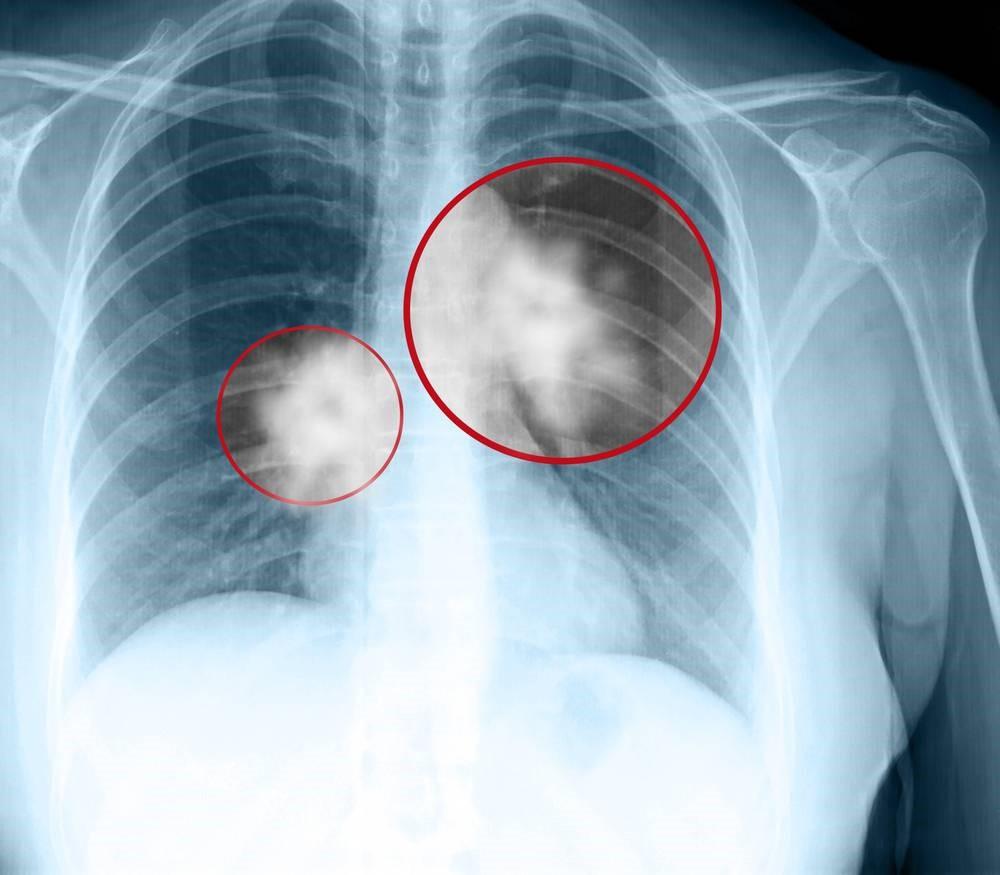

| Так выглядит на рентгеновском снимке рак легких |